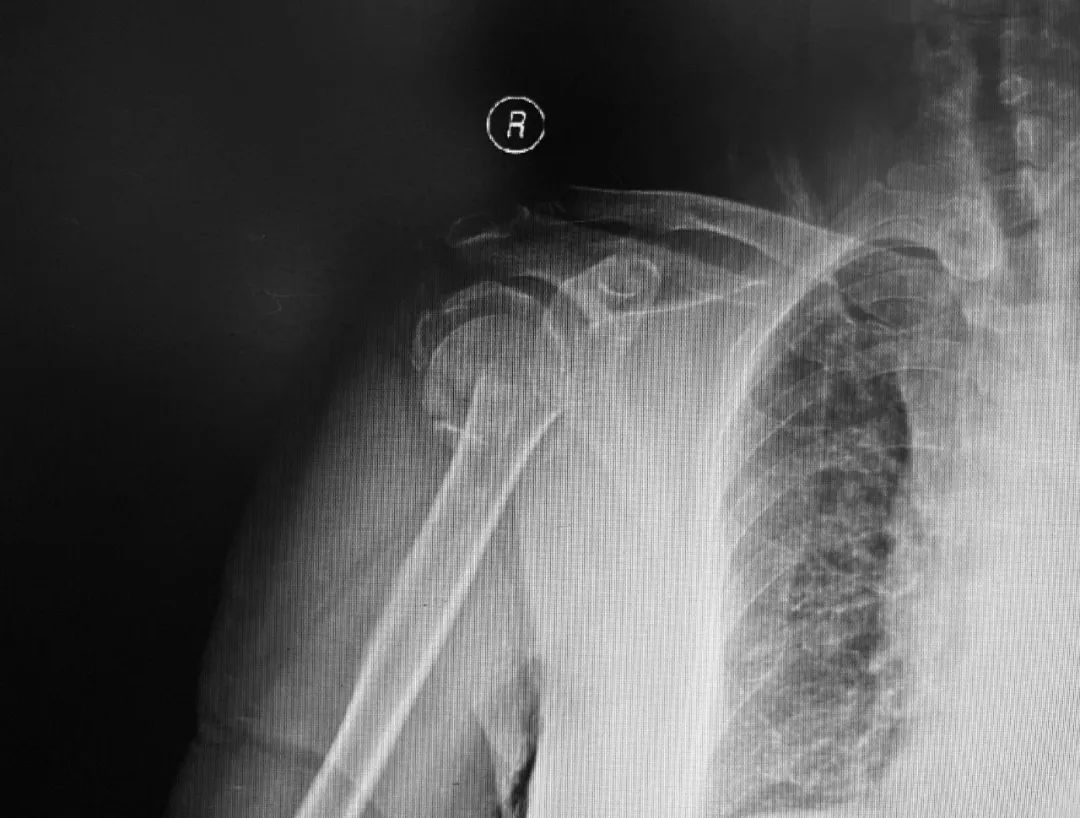

患者女性,72岁,不幸在两周前因骑车摔伤导致右侧肱骨近端粉碎性骨折,外院予其支具固定、保守治疗。为了尽快缓解骨折带给自己的痛苦,并寻求更好的远期功能结果,患者来到积水潭医院寻求救治。蒋协远院长带领的智能骨科团队经过仔细查体和阅读影像资料,共同商讨该病例后,蒋院长认为本患者年龄较大,平时身体状态良好、基础病不多,加之患者自己手术意愿较为强烈,决定为她实行机器人辅助下的反式人工肩关节置换术。

术前,患者的影像资料。